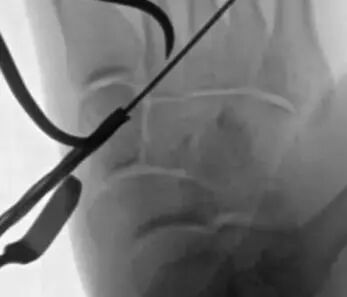

使用导丝将可调袢从外侧穿过到内侧并复位,内侧支撑钛板位于第二跖骨的基部和内侧。牵拉使内侧支撑钛板紧贴骨质,对侧用带线锚钉完成锁定。